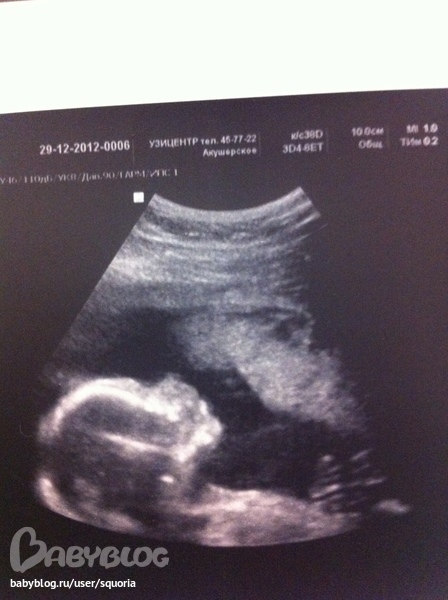

Внеплановое УЗИ. 18 недель 1 день.

Вчера с мужем сходили на внеплановое УЗИ. Хотели сделать себе подарок к Новому году и узнать все-таки уже точно, кто там у нас поселился. Малыш во время УЗИ спал. Изредка шевелил ножками и ручками. Все показатели в норме. размеры соответствуют сроку беременности. Впервые увидела как он шевелится! Опять пустила слезу от счастья! Пол нам долго врач не мог показать во всей красе, детеныш прикрывался ножками. Пришлось немного поворочаться. И, о чудо! Показали и сфотографировали нам мужское достоинство! "Вердикт" 12 недель оправдался. У нас будет сыночек! Самый-самый сладенький ребеночек на планете! Шевелений вроде пока не ощущаю. Точнее ощущаю что-то, но списываю на кишечник, пока не радуюсь, жду когда почувствую совершенно четко. Деть на прощание помахал нам пальчиками и все также продолжал сладенько спать. А мы пошли. Точнее я полетела на крылышках счастья. Теперь с нетерпением жду появления своего крошки!